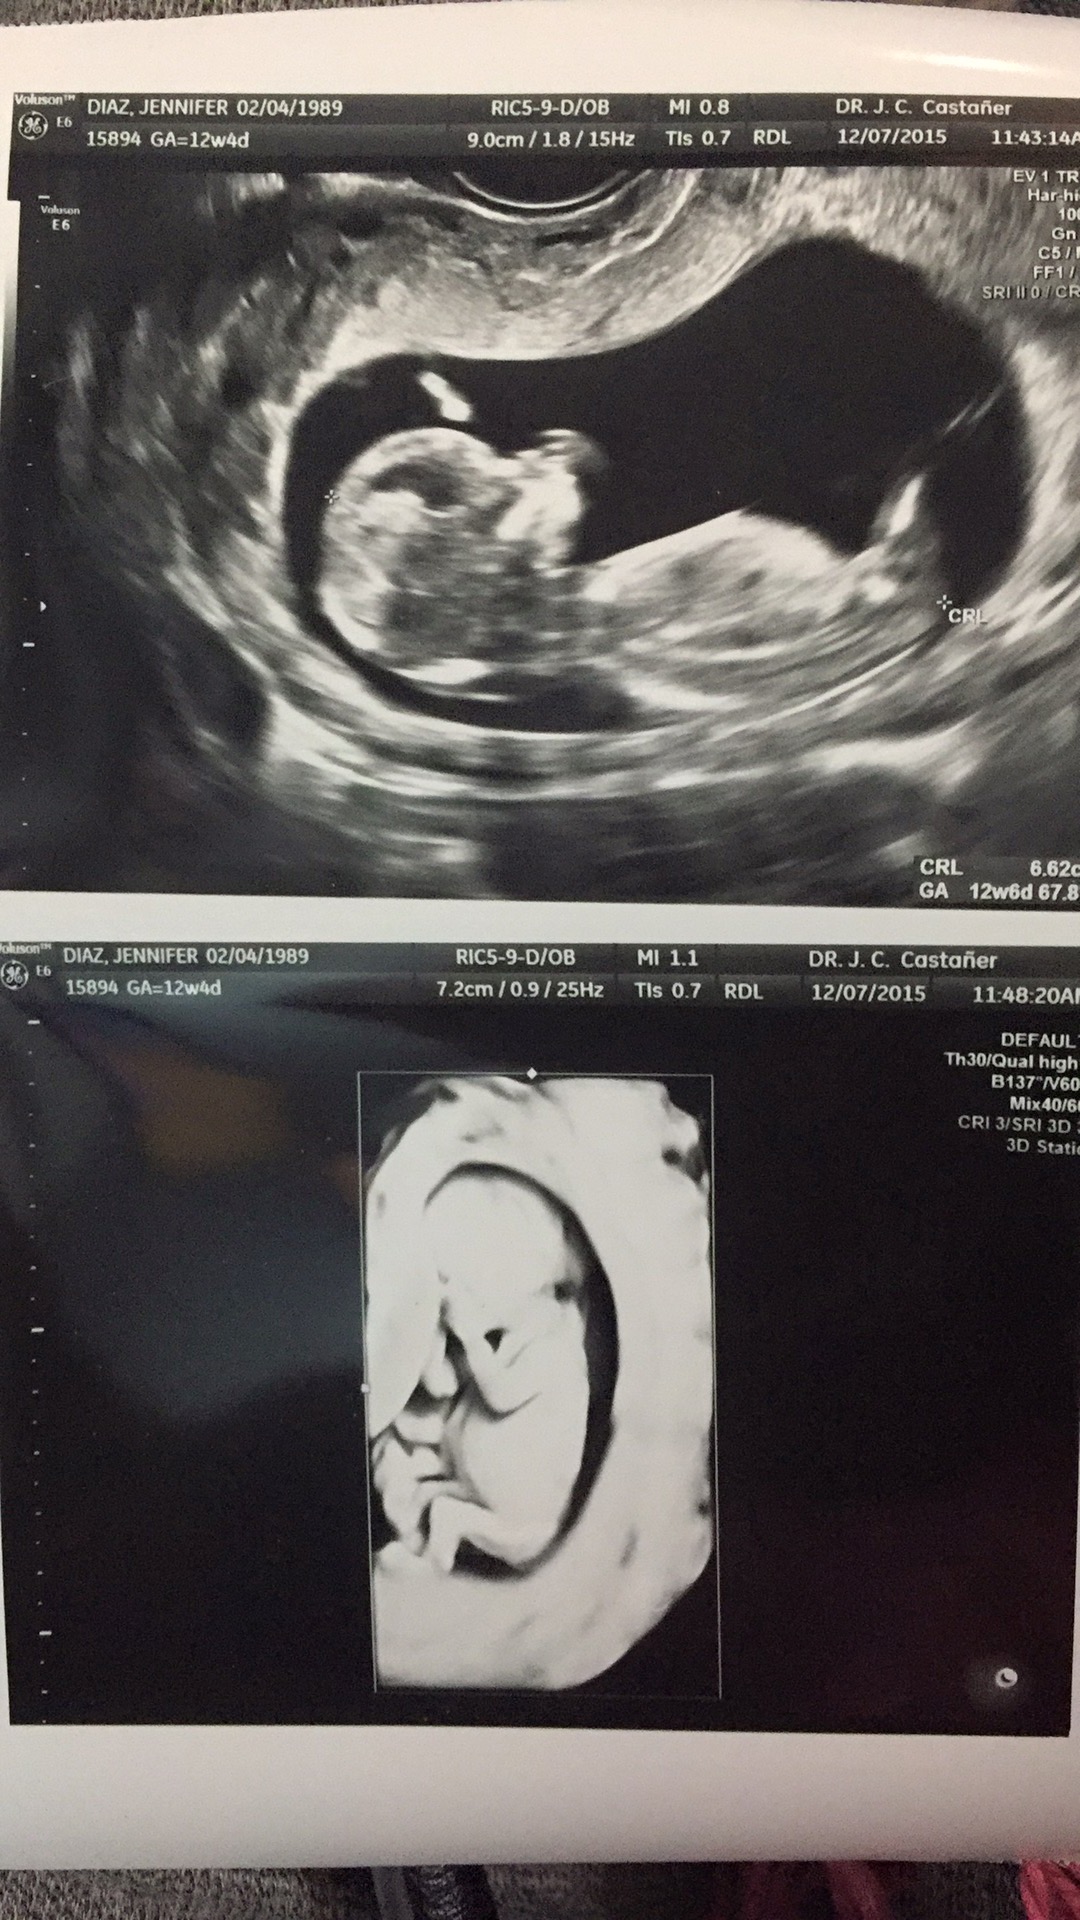

Had my NT scan today. Such a huge difference from my 7 week ultrasound. It actually had arms and legs this time!!

12w 1d

I ask because you have a textbook nub and didn't want to tell you if you if you didn't want to know lol it's basically one of the only theories that are pretty accurate. (I hope I don't get flamed)

I have actually been thinking about this but I have no clue if it's nub or leg (maybe even cord). We didn't notice it while we were in the scan, only after we got home. I told my husband about it because he's been convinced it's a boy since we got pregnant (his main reasoning was that since HE is a boy, baby will be a boy) :)

I don't think you'll get flamed, at least not from me. I have some OB/GYN friends who actually told us about this method a few weeks ago, so I'd say it's pretty valid. It totally slipped our minds once we were at the appointment. I may have to run this picture by them.

I did a ton of research on this when I was pregnant with my son and I would be absolutely amazed if it wasn't a boy with how clear that image is. I'm curious to see what your friends say, keep me updated!